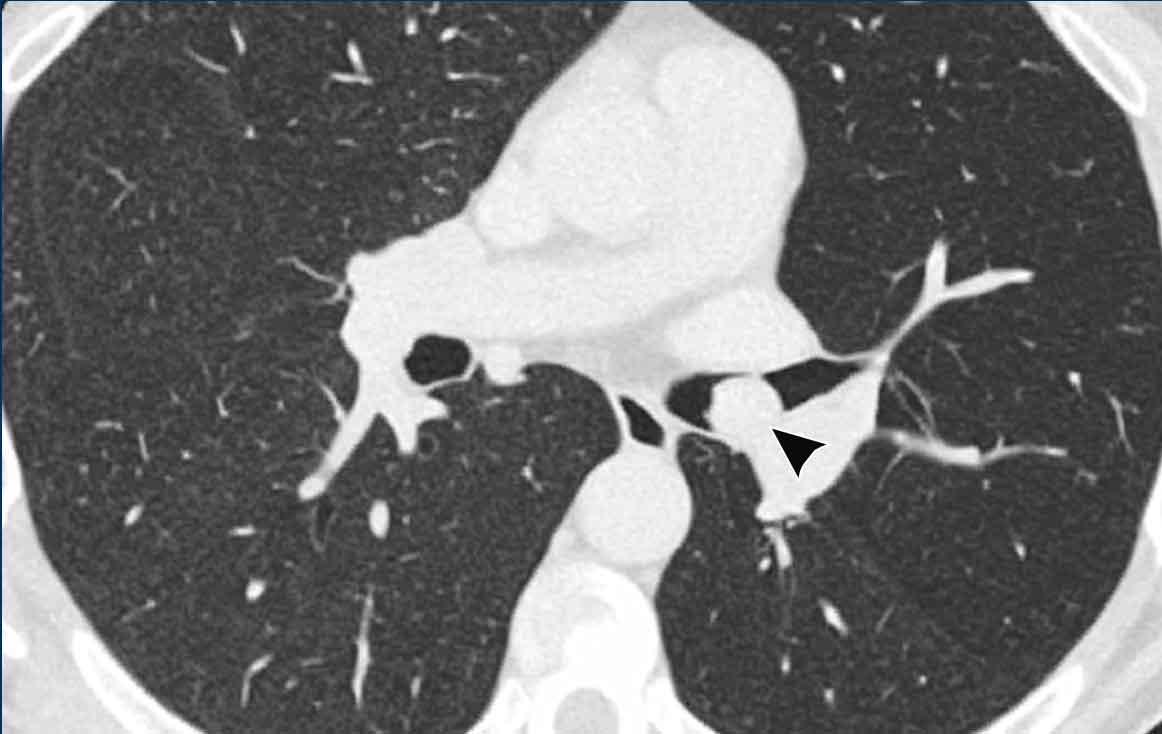

Khối bờ rõ ở phế quản gốc trái ở nam giới 39 tuổi.

Tiếp tục xem PET-CT…

PET-CT 68Ga-Dotatate cho thấy hấp thu mạnh, xác nhận nguồn gốc tế bào thần kinh nội tiết.

U carcinoid xuất hiện ở các đường thở trung tâm hơn (mặc dù hầu như không bao giờ ở khí quản) cũng như ở các đường thở ngoại vi hơn, kéo dài đến tận một phần ba ngoài của phổi.

Trên CT, u carcinoid là tổn thương bờ rõ, thường tăng tỷ trọng trên CT sau tiêm thuốc cản quang do bản chất tăng mạch máu.

Vôi hóa có thể gặp trong một số ít trường hợp.

Các thay đổi sau tắc nghẽn thường gặp do tắc nghẽn lòng đường thở, và có thể là lý do phát hiện bệnh.

Một số tổn thương cũng có thành phần ngoài lòng đường thở, điều này loại trừ khả năng điều trị triệt căn hoàn toàn qua thủ thuật nội soi.

Trong những trường hợp này, cần phẫu thuật cắt bỏ theo giải phẫu.